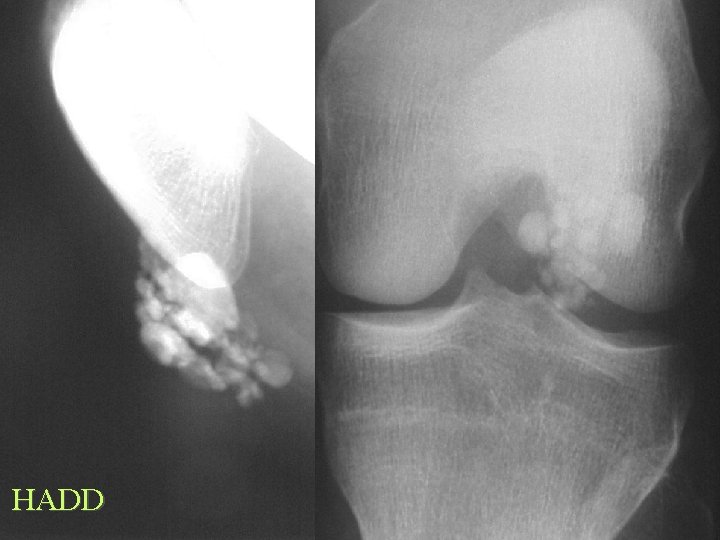

Ossification Traumatic Tendons and Ligaments • Calcification common, Ossification rare • • • MCL knee - Pellegrini-Stieda Coracoclavicular Achilles tendon Supraspinatus Stylohyoid ligament XS - Eagle syn.

SST Oss

Calcification By site Tendons and Bursa • Calcium hydroxyapatite deposition disease • Calcium pyrophosphate dihydrate deposition disease

Calcification By site Tendons and Bursa CPPD • Linear • Articular • Achilles, Quads, Tri • Ass. arthritis MCPCDD • • HADD Rounded Amorphous Tendons and Bursa Rotator cuff